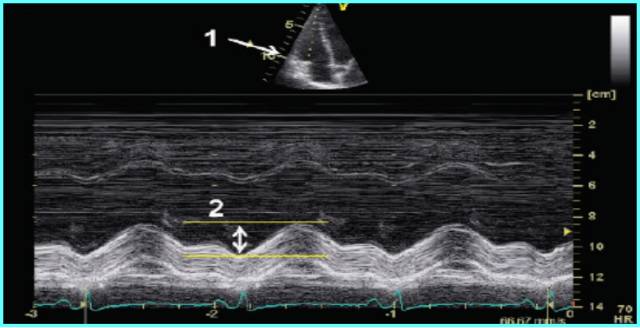

测量位置:胸骨旁左心室长轴,或二尖瓣瓣尖水平左心室短轴切面。

测量内容:室间隔厚度、左心室后壁厚度、左心室内径。

测量时相:收缩末期、舒张末期。

直接二维测量或在二维引导下的M-型曲线上测量。

ASE推荐于二尖瓣瓣尖水平胸骨旁短轴切面直接测量或采用M型曲线测量。M-型超声时间分辨率好。有助于帮助二维超声区分临近左室后壁的肌小梁、室间隔左室面的假腱索、室间隔右室面的调节束等结构。即使采用二维引导也可能无法保证M-型取样线完全垂直于室间隔和左心室后壁。